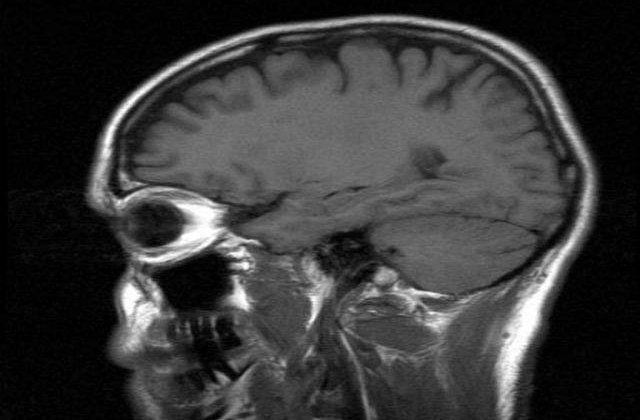

"Creierul uman functioneaza mai incet la varste inaintate deoarece am acumulat mai multa informatie de-a lungul timpului", spune Michael Ramscar, coordonatorul cercetarii.

Echipa de cercetatori de la Tübingen University din Germania s-a folosit de computere pentru a reproduce diferite stadii ale memoriei unui adult. Modelele create pentru computere au fost "hranite" in fiecare zi cu o anumita cantitate de informatii (la fel cum se intampla in cazul adultilor tineri), dar, odata ce dispozitivele strangeau mai multa informatie, performanta lor reflecta performanta persoanelor in varsta, potrivit studiului, care a fost publicat in revista Topics in Cognitive Science.

Cercetatorii au ajuns la concluzia ca, in cazul persoanelor in varsta, creierul nu se deterioreaza de-a lungul timpului, din cauza imbatranirii, asa cum se credea initial, ci functioneaza mai lent din cauza cantitatii mari de informatii care s-au acumulat.